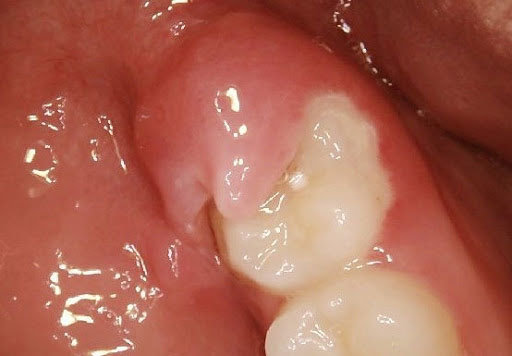

Acute inflammation of the gingiva and/or mucosa surrounding a partially erupted tooth. Also known as operculitis.

Pericoronitis is a gum condition characterized by irritation and inflammation caused by the partially erupted crown of a tooth.

Inflammation of the gum around the crown of a tooth. Pericoronitis usually affects a partially impacted tooth, typically the third molar (wisdom tooth). If there is an opposing tooth, it may be difficult and painful to close the jaw. The infection produces swelling of the gum and may result in fever and continual pain. When left untreated, pericoronitis can spread into surrounding gum and bone tissues, presenting serious complications. It is generally caused by the presence of food particles and the subsequent growth of bacteria in the spaces between the gum and the tooth. The infection can be treated with antibiotics. If pericoronitis recurs and becomes chronic, an oral surgeon may be needed to remove some of the gum tissue and allow the tooth to emerge. If there is not adequate room for the tooth to develop and emerge normally, it may need to be extracted. Wisdom teeth are normally extracted when the tissue around them is infected. This is due to the difficulty in keeping the gums clean in that hard-to-reach location.